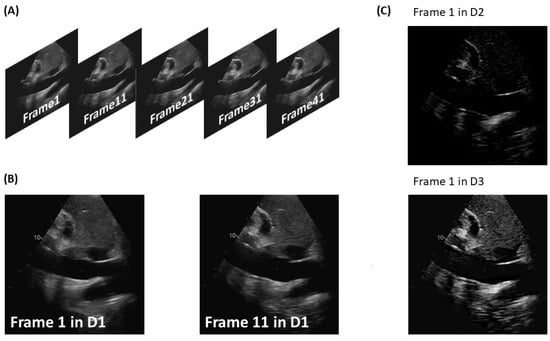

Figure 1 shows two frames from each augmented dataset.

Figure 1.

Process of creating the augmented datasets. (A) Frames extracted from a US video and segmented by the operator. (B) Example of a pair of consecutive frames. (C) Examples of images included in the two datasets obtained applying Equation (1): dataset 2 provides information on IVC movement; dataset 3 includes images including both information on the anatomy and on the movement of tissues.

The original dataset D, consisting of 8334 segmented frames, was used to create three comparable datasets, referred to as D1, D2, and D3. These datasets were used to train and test our detection method. For each subject, consecutive pairs of images were considered, excluding frames that did not have a corresponding frame after a pitch of 10 frames. D1 was created by collecting all the frames. On the other hand, D2 and D3 were obtained by applying the following equation:

where is the target frame on which to detect the IVC.

The frames of D2 were obtained by setting : in this way, information on the movement of tissues was obtained by calculating the difference between consecutive frames. The information obtained from this dataset is believed to be useful in identifying the IVC, as it exhibits significant respirophasic movements. D3 was generated using : both anatomy and movement information were captured, as each image is the sum of the target frame and the movement .